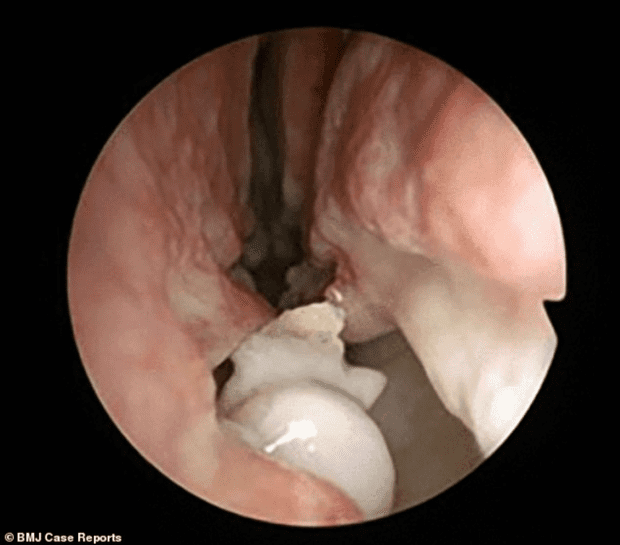

Allí, los profesionales descubrieron que en el interior de sus fosas nasales había crecido un diente. Tras realizarse los estudios correspondientes, se constató que es deformidad se trabaja era en realidad un tumor.

Según dio a conocer el centro médico, esta condición se la identifica como hiperdoncia o dientes supernumerarios y afecta a sólo el 4 por ciento de la población humana, pero que crezca con un desvío hacia arriba en el 0.1 por ciento de las personas.